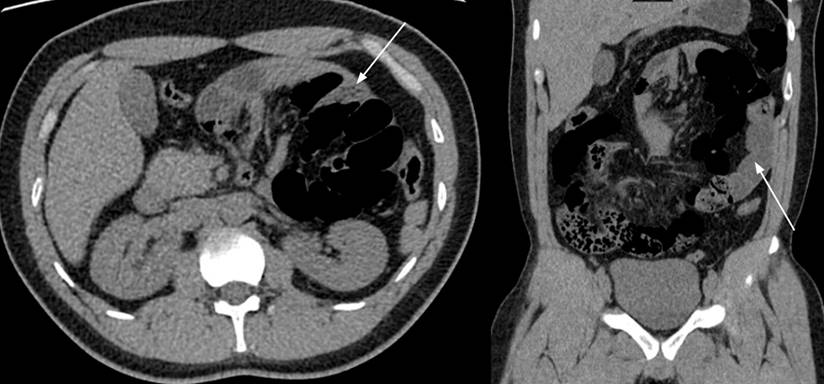

This is a 29-year-old male patient with no medical or surgical history. He was admitted to the emergency department due to a 24-hour clinical profile of abdominal pain of sudden onset, colic type, located in the mesogastrium and left flank, accompanied by abdominal distension and emesis, radiating to the left paravertebral region and the left iliac fossa. Physical examination documented sinus tachycardia, distended abdomen, and pronounced deep palpation pain in the left hemiabdomen, with no signs of peritoneal irritation. Paraclinical studies showed leukocytosis (15,000 cells/μL), neutrophilia (12,750 cells/μL), and elevated C-reactive protein (16 mg/dL). Initially, it was suspected to be urolithiasis with obstructive effect. The patient underwent a simple computerized tomography urogram (uroCT), which showed a conglomerate of intestinal loops located towards the left hemiabdomen with diffuse intestinal edema and scarce fluid between the loops (Figure 1).

Many PH cases are diagnosed incidentally on imaging, laparotomy, or autopsy.2,5,9 Simple radiographic studies are not very specific, showing signs of intestinal obstruction with a conglomeration of intestinal loops towards the left side of the upper abdomen.3 Contrasting studies such as tomography document a mass of regular, smooth edges with loops of small intestine encapsulated in the upper hemiabdomen, described as Donnelly’s border. Additionally, anomalies can be seen in the mesenteric vessels consisting of their congestion, crowding, twisting, and stretching.4,5,10

If the PH is left-sided, we can observe a group of intestinal loops delimited by the pancreas, stomach, and ascending portion of the duodenum, to the left of the ligament of Treitz, behind the pancreatic tail, which displaces the inferior mesenteric vein to the left or between the transverse colon and the left adrenal gland. When the PH is right-sided, the accumulation of loops is located inferolateral to the descending portion of the duodenum, and we can observe an afferent loop of the jejunum and an efferent loop of the jejunum or ileus through the entrance hole of the Waldeyer’s fossa.3,5 The sensitivity and specificity of tomography are approximately 63% and 76%, respectively.11 Diagnostic laparoscopy can be very useful in cases where the diagnosis cannot be verified with images.2